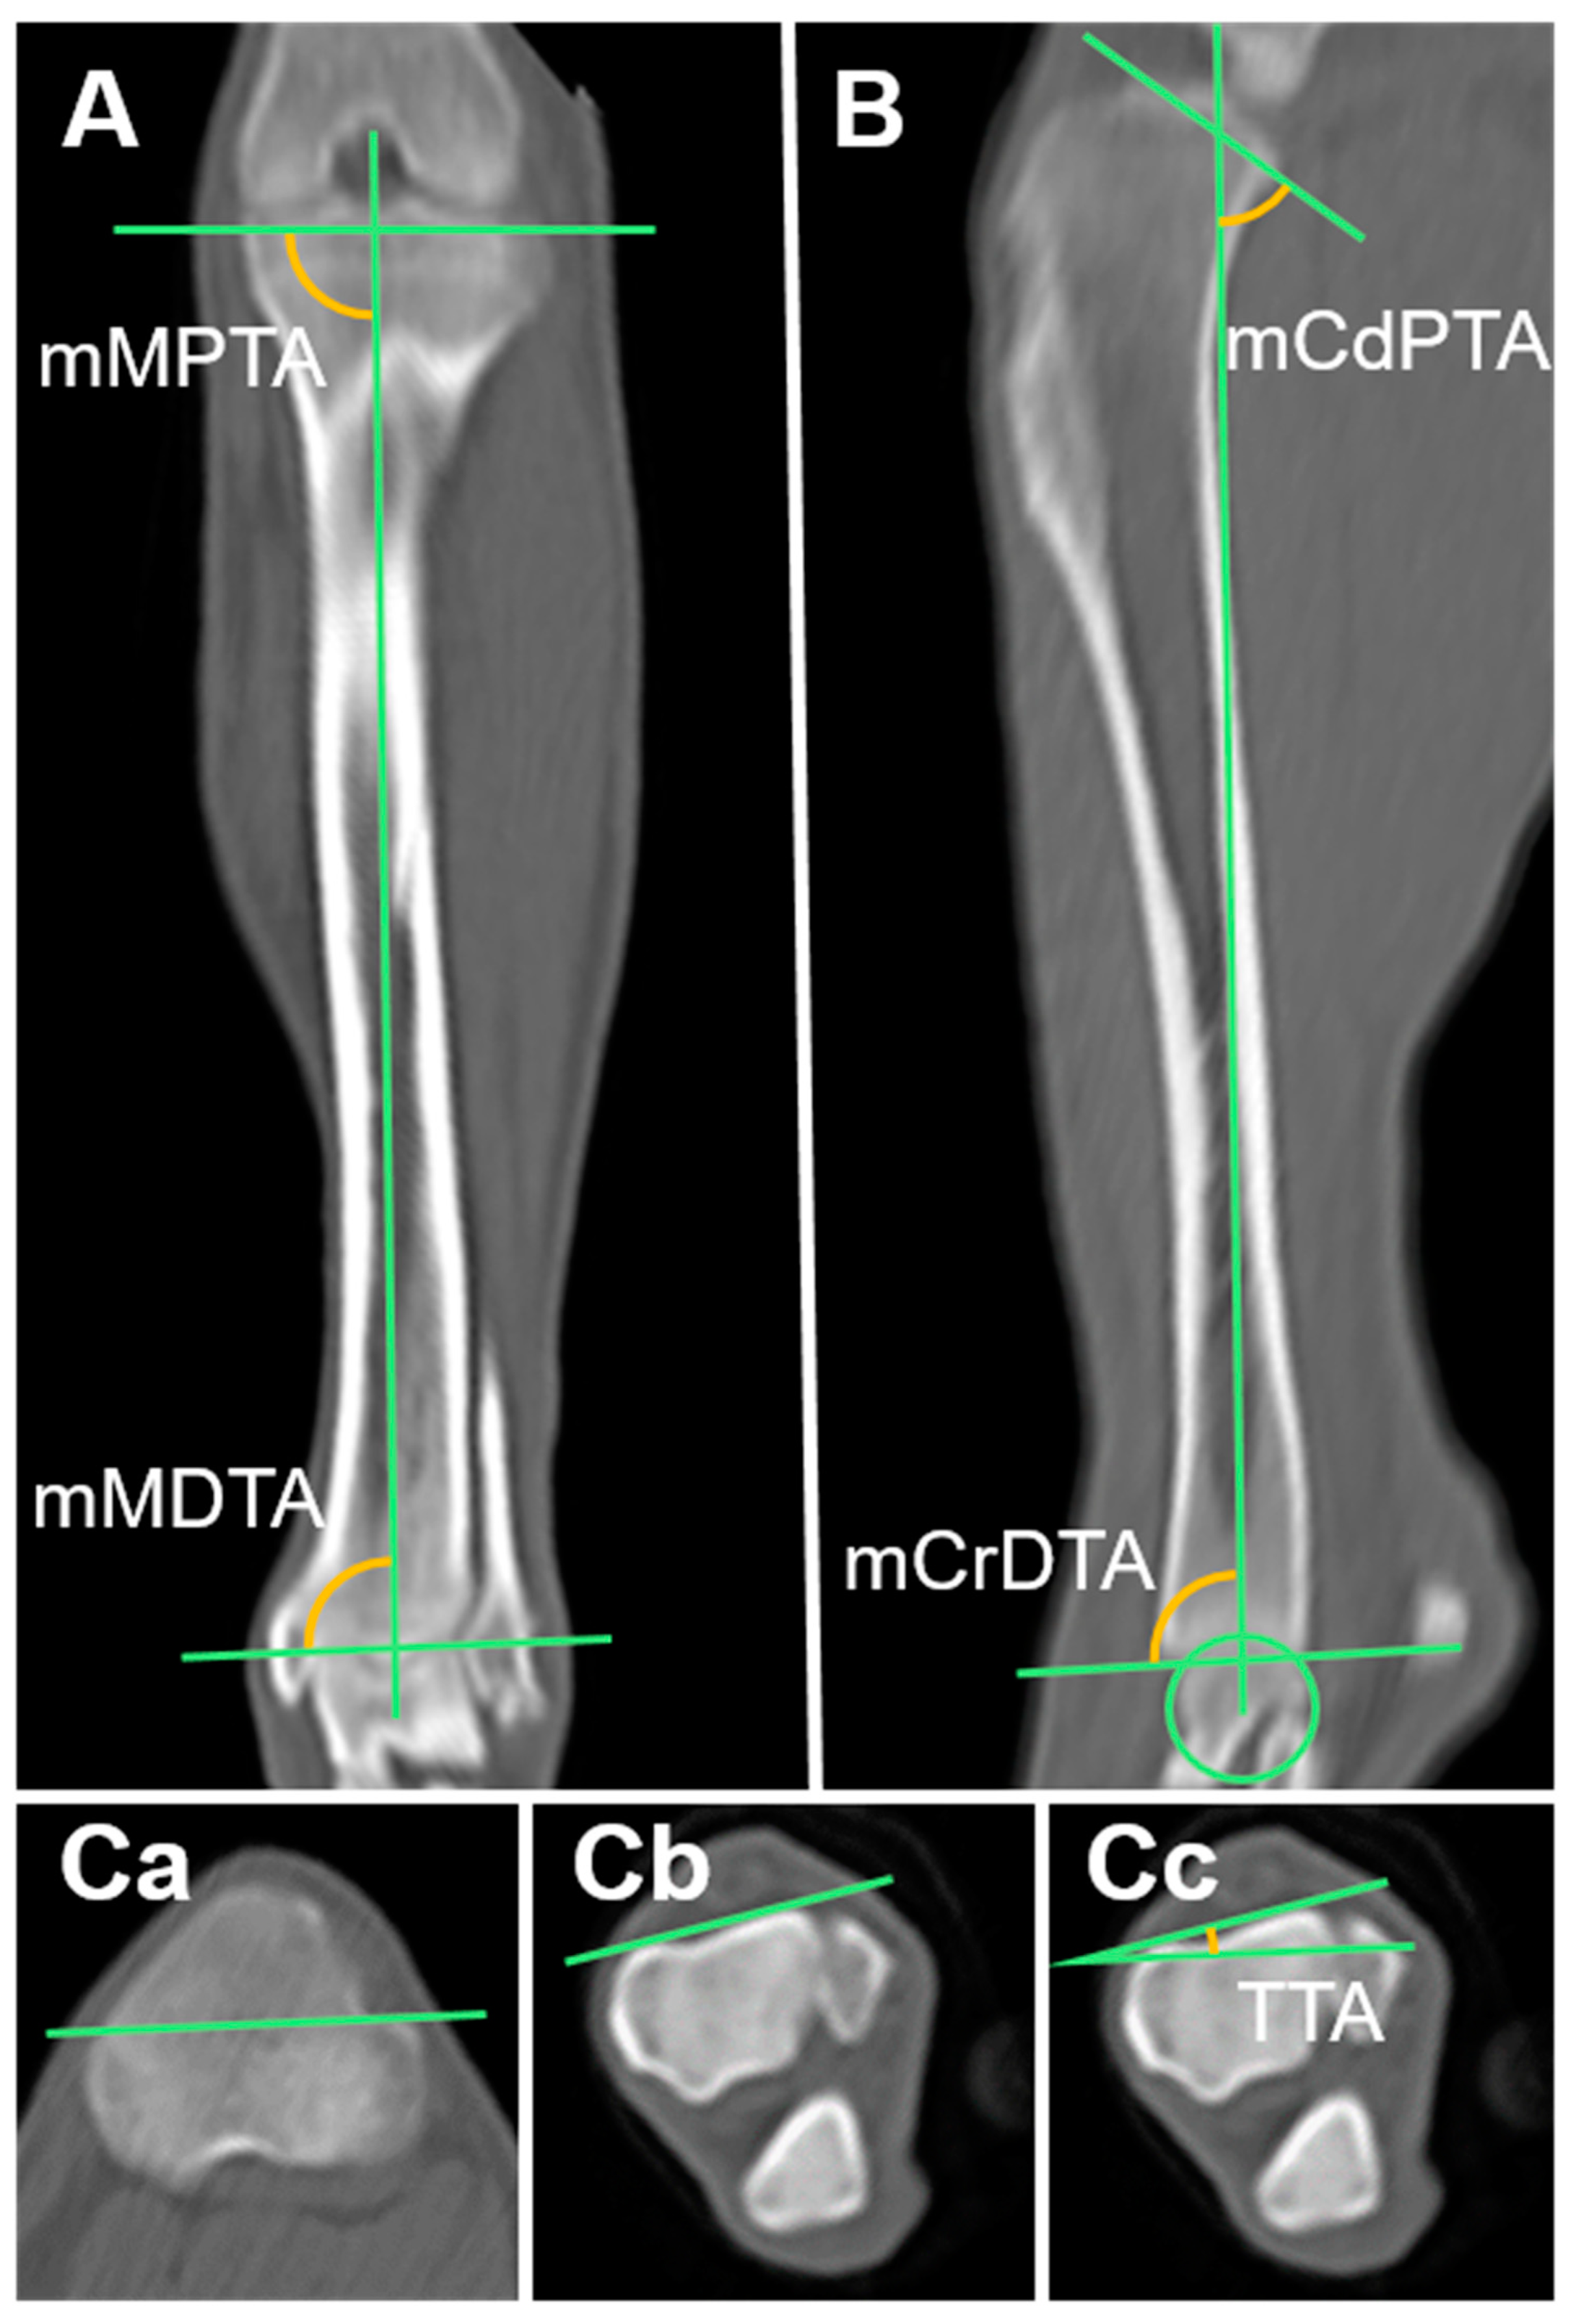

2.3.12. Mechanical Medial Proximal Tibial Angle (mMPTA) and Mechanical Medial Distal Tibial Angle (mMDTA)

2.3.13. Mechanical Caudal Proximal Tibial Angle (mCdPTA), Mechanical Cranial Distal Tibial Angle (mCrDTA), and Tibial Plateau Angle (TPA)

2.3.14. Tibial Torsional Angle (TTA)